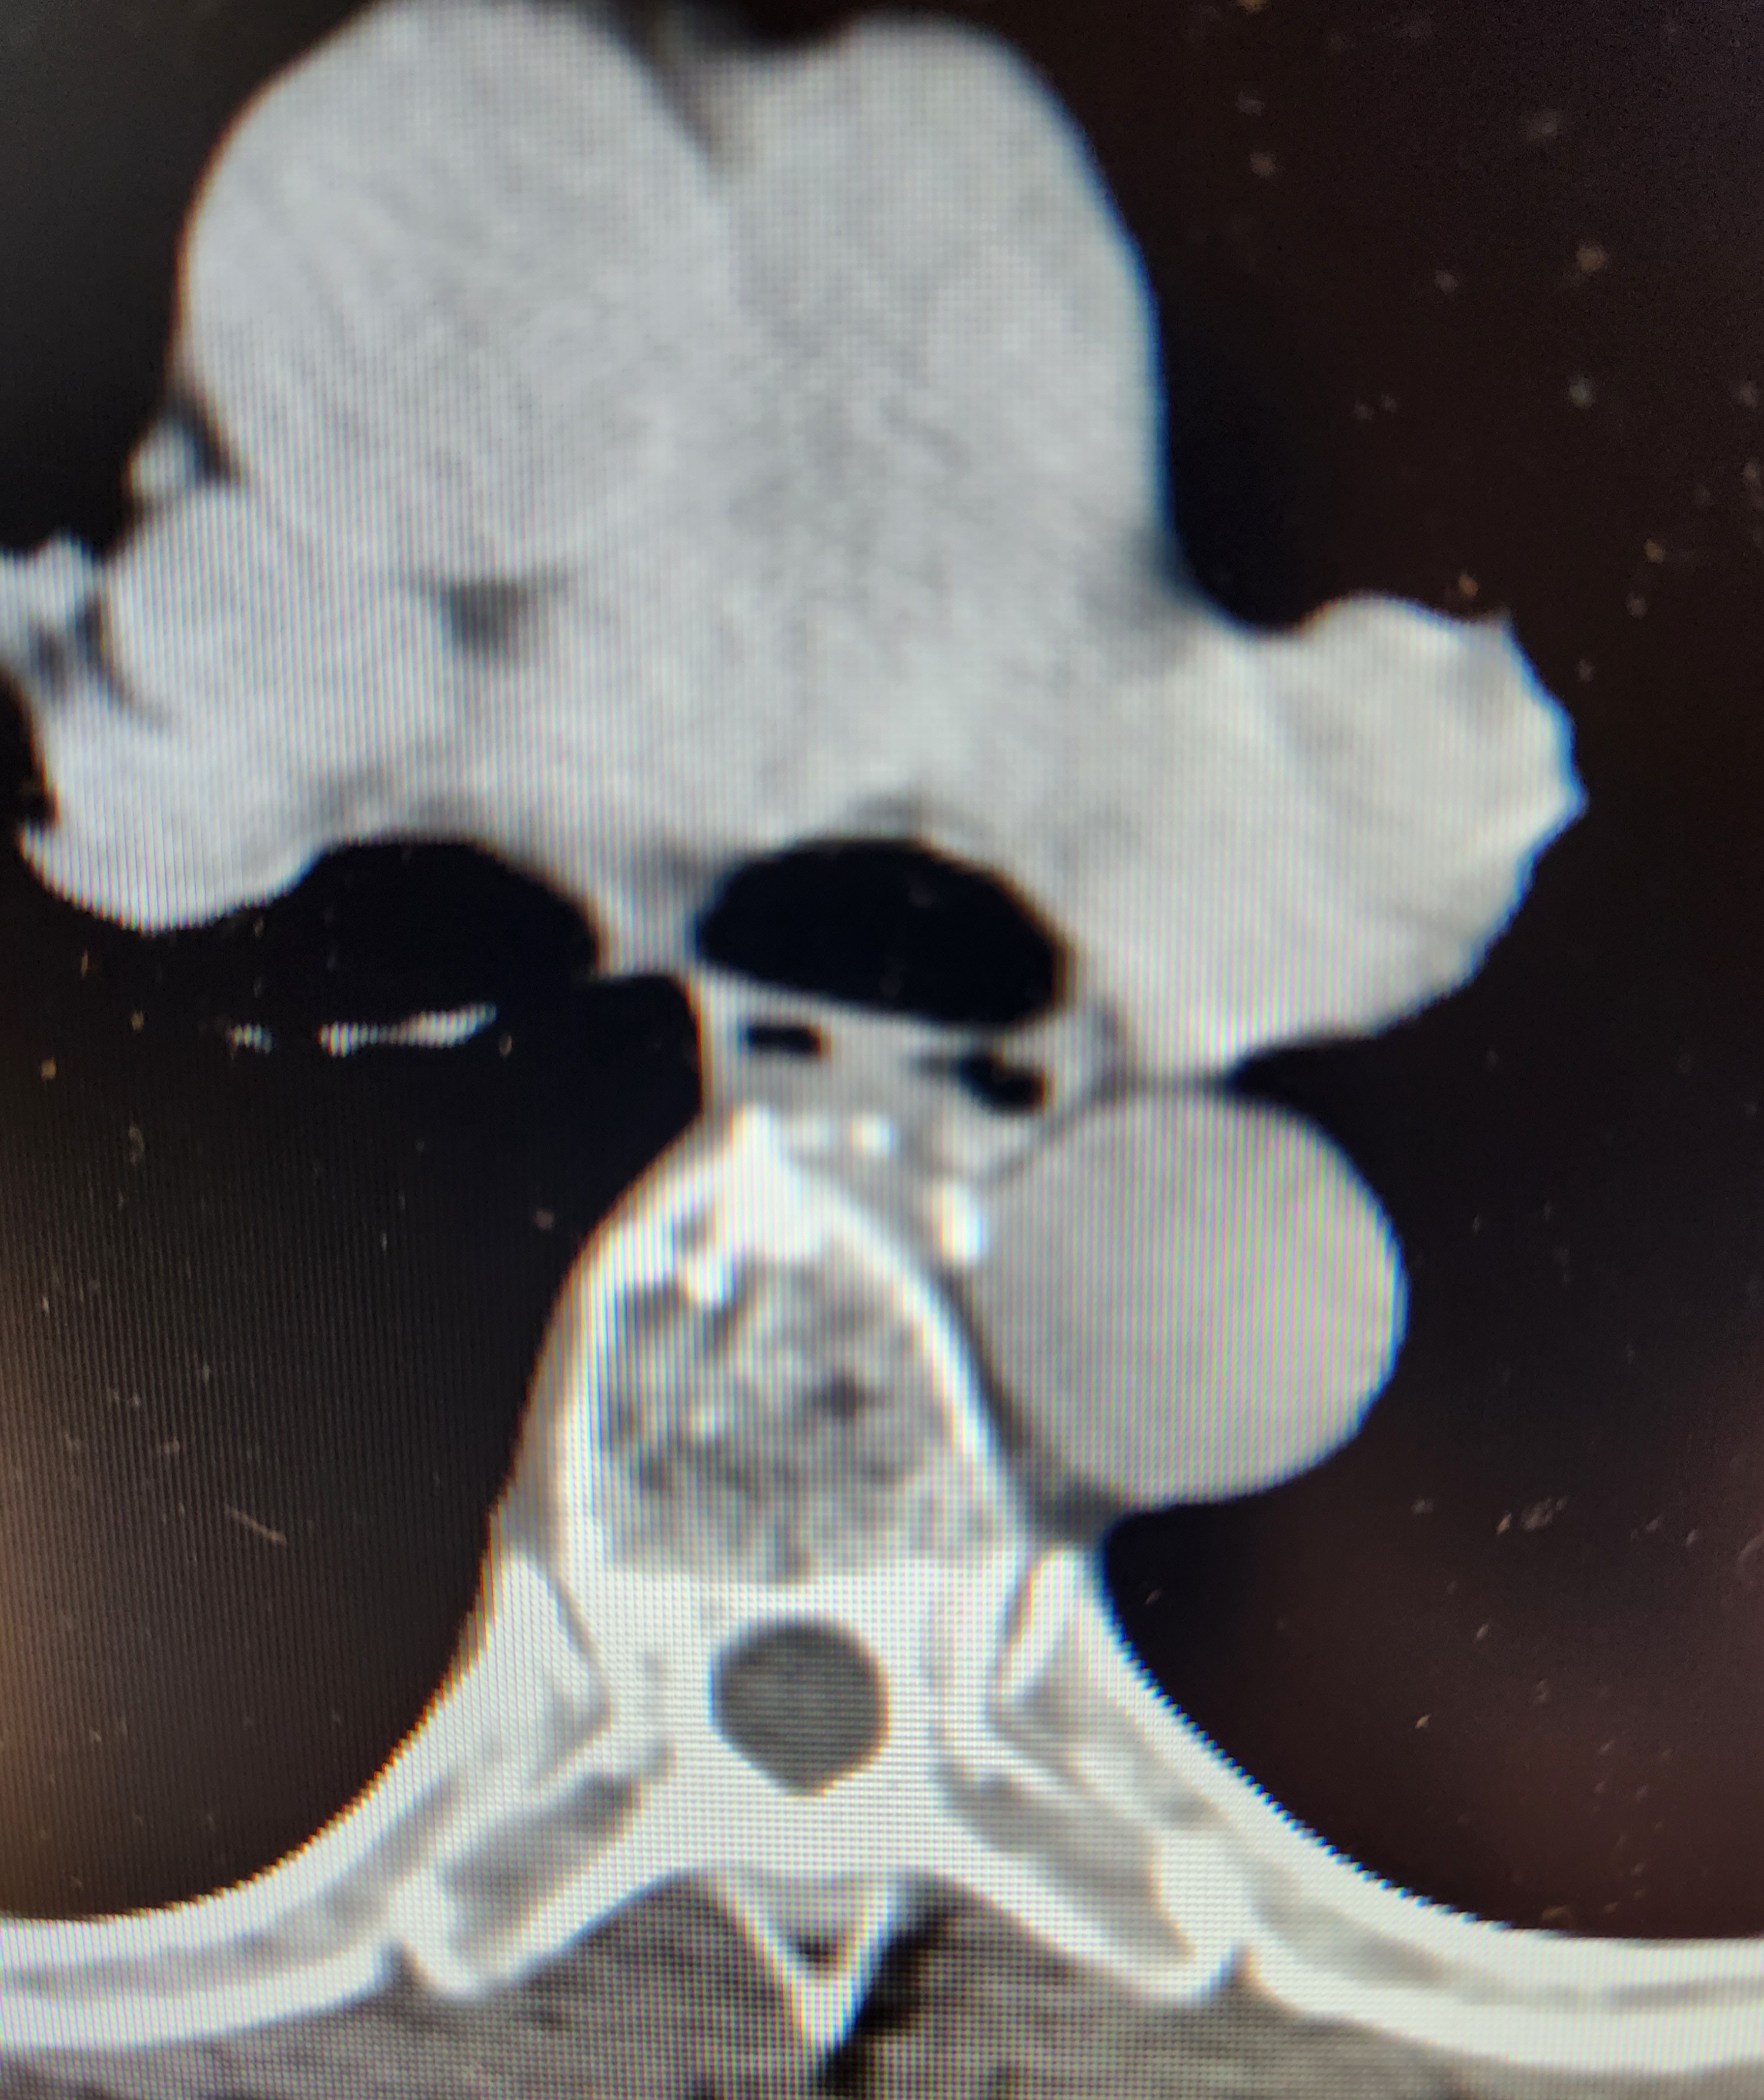

File: 20230526_104837.jpg (1.96 MB, 3000x3572)

>>64449187

We have tools on the scanner to measure objects for cancers and cyst and such and used those to measure the bullet at the time. It matched about what a 45acp bullet should be, but this was 2 years ago and I don't have any pictures of those measurements so you're either going to have to measure the ribs and vertebrae and then based on that measurement and the average size of those pieces of anatomy get a measure of the bullet yourself, or just trust me on this one. Here is another internal picture of the same patient below the bullet if you want to put in your own legwork. I put in enough leg work drawing diagrams and finding articles of FMJ overpenetration causing a death only for folks to go "nuh uh", so this will be my last post on the subject.

It's worth noting that there are bullet fragments seen around the patient's right scapula seen here >>64449110 (remember, in radiology anatomy is flipped left/right) so as to your barrier penetration that could be the cause. Also worth noting is that the bullet is now facing the direction it entered, meaning it tumbled a bunch after impact. Quality hollow points are designed to penetrate things like auto glass and still travel through a persons arm and chest to the heart.

Tl;dr for all of this is just buy some goddamn hollow points and make sure they work with your gun and be done with it.